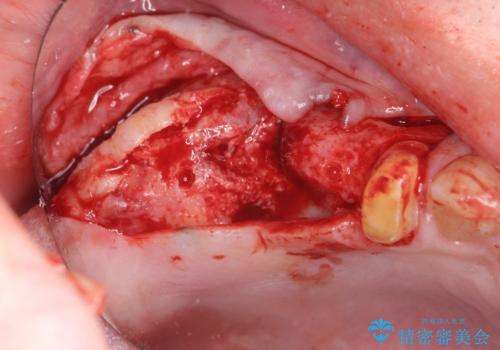

- 破折した歯を放置し、骨が高度に吸収した状態でインプラント治療を希望し来院されました。

インプラントを適切な位置に埋入し仕上げた後にも清掃性を高めるには、必要十分な骨となだらかな歯肉形態の獲得が必要です。

インプラント埋入時に骨の造成を、2次手術時に歯肉の凹みを整え厚みを一定にするような治療を進めていきます。

骨の造成、歯肉を整えたことで、術前山形にえぐれていた歯肉形の態はなだらかになり清掃しやすい状態へと整備することができました。